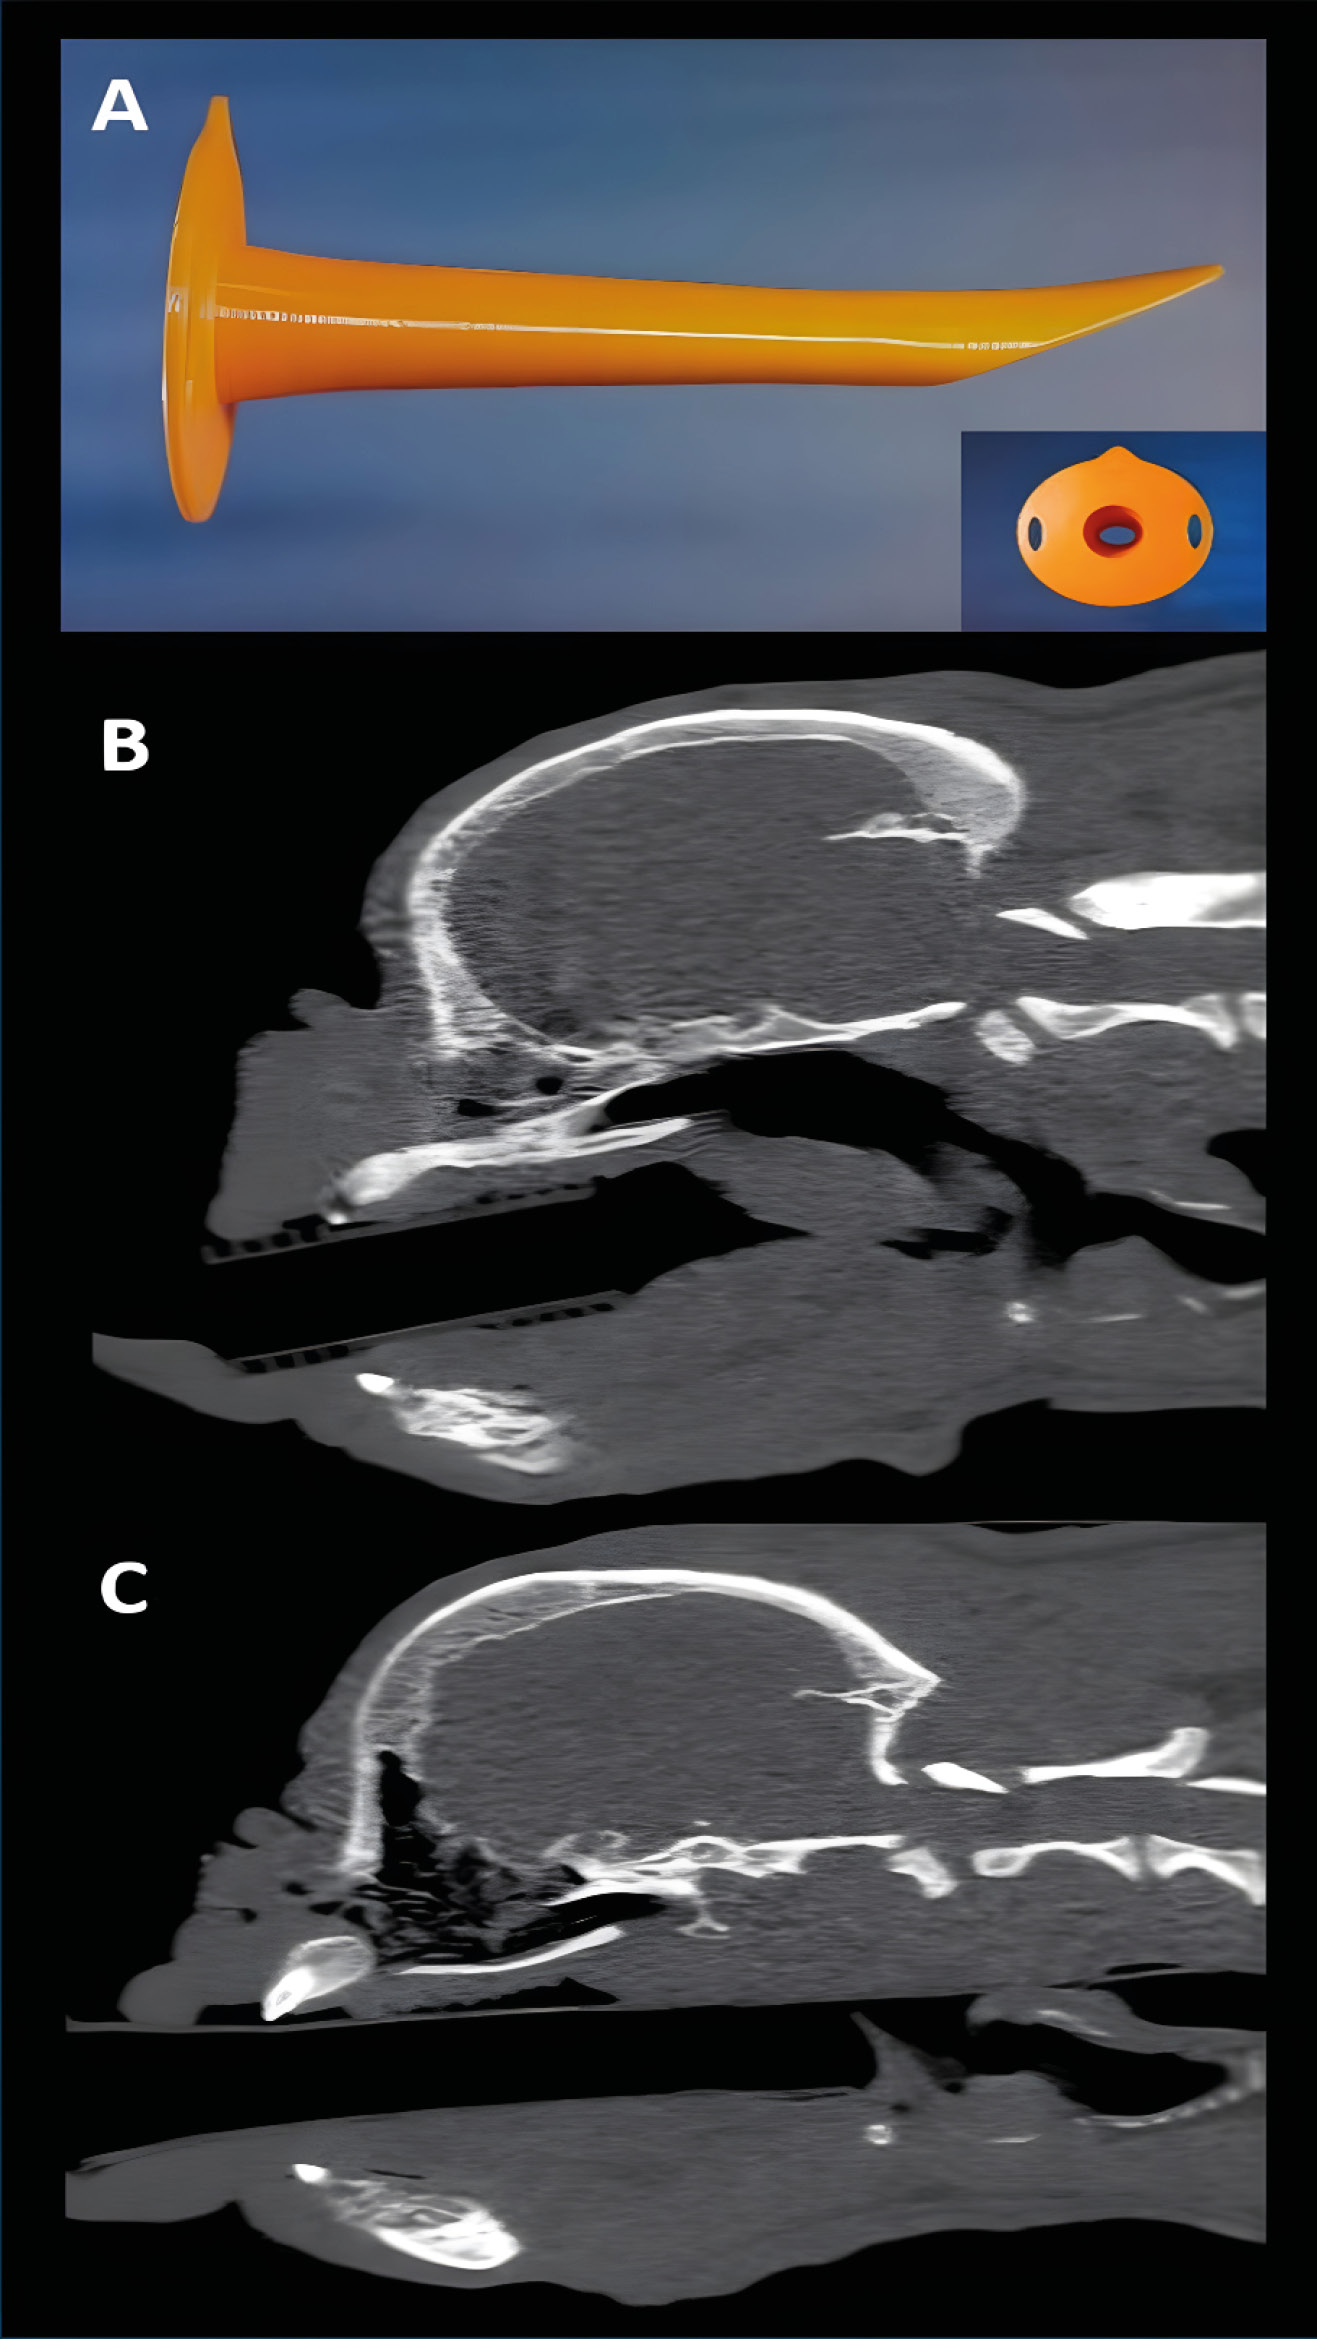

Uno de los dispositivos supraglóticos más utilizados en humana son las mascarillas laríngeas. Aunque al principio se estudió el uso de mascarillas laríngeas de humana en pequeños animales, hace unos años tenemos en el mercado mascarillas laríngeas específicamente diseñadas para la anatomía del gato, el conejo y el perro. La mascarilla laríngea de la especie canina ha sido la última en ser desarrollada y tiene un canal que permite el paso de una sonda para aspirar secreciones esofágicas y disminuir la posibilidad de que el reflujo pase a tráquea (imagen 3).

Su colocación es fácil, ya que solo requiere abrir la boca del animal, estirar la lengua e introducir el dispositivo lubricado hasta que está colocado sobre la entrada de la tráquea (imagen 4). La cúpula queda por encima de las estructuras laríngeas, por lo que, en principio, estas no sufren traumatismo (imagen 5). Para estar seguros de que la colocación es correcta, debemos usar el capnógrafo y observar una curva de capnografía perfecta.

En conejos, debido a su mayor dificultad para intubación endotraqueal comparada con los perros y los gatos, la mascarilla laríngea se ha convertido en una opción tanto para su utilización como dispositivo de manejo de vía aérea como para facilitar la intubación.

Aunque pueden ser de mucha utilidad en pacientes en los que se realicen anestesias cortas o procedimientos poco invasivos (p.ej., TC), debemos tener en cuenta varias limitaciones potenciales. Una de ellas es que, aunque esté correctamente colocada al principio, puede desplazarse si movemos el paciente y dejar, por tanto, una vía de entrada de secreciones a la tráquea, lo que puede dar lugar a complicaciones como neumonía por aspiración, etc. De la misma forma, si la mascarilla está sellando perfectamente la entrada de la tráquea, podemos realizar una perfecta ventilación a presión positiva. Pero, si no está bien sellada, aunque podamos producir una buena ventilación en el paciente, cierto volumen llegará al esófago y estómago, produciendo timpanismo y una mayor posibilidad de reflujo gastroesofágico.